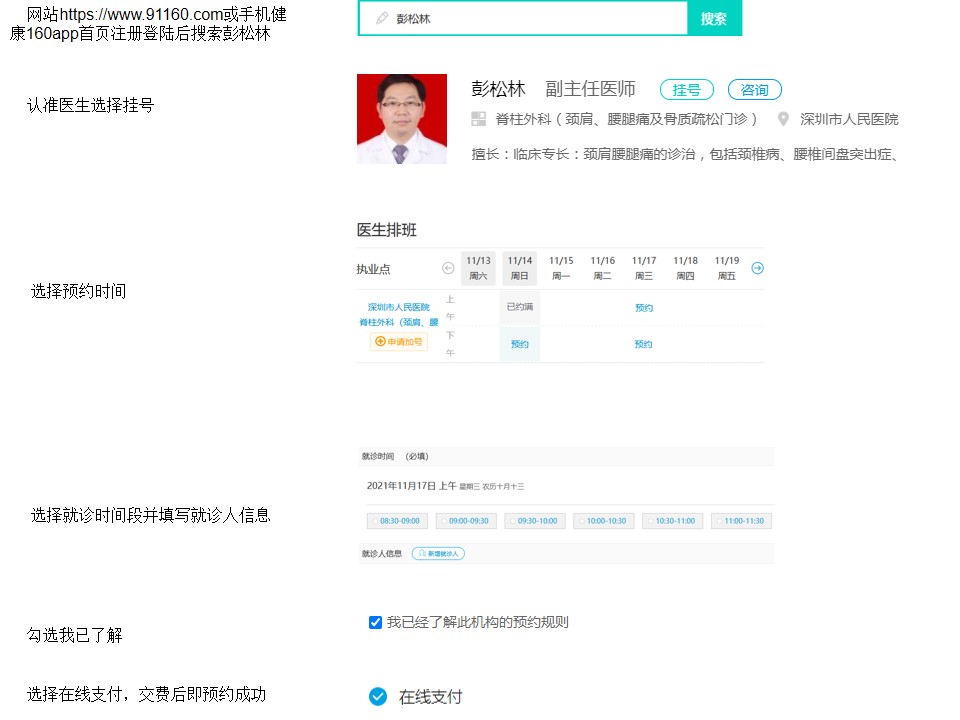

160挂号: